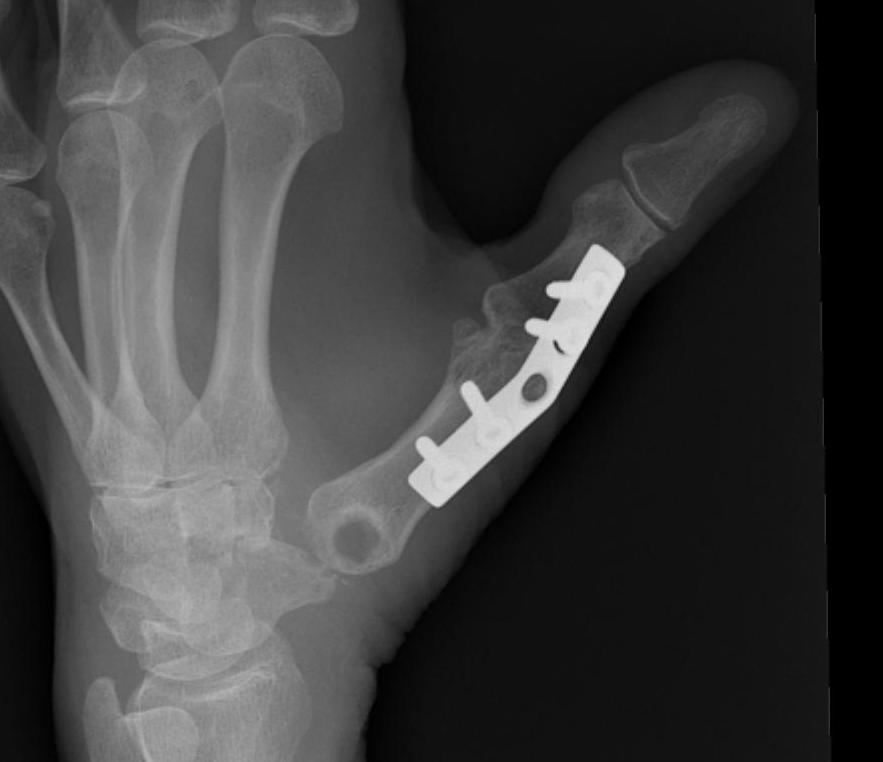

Type IV - Gamekeepers

- due to MCPJ synovitis

- stretches UCL

- either synovectomy / UCL reconstruction

- or fusion